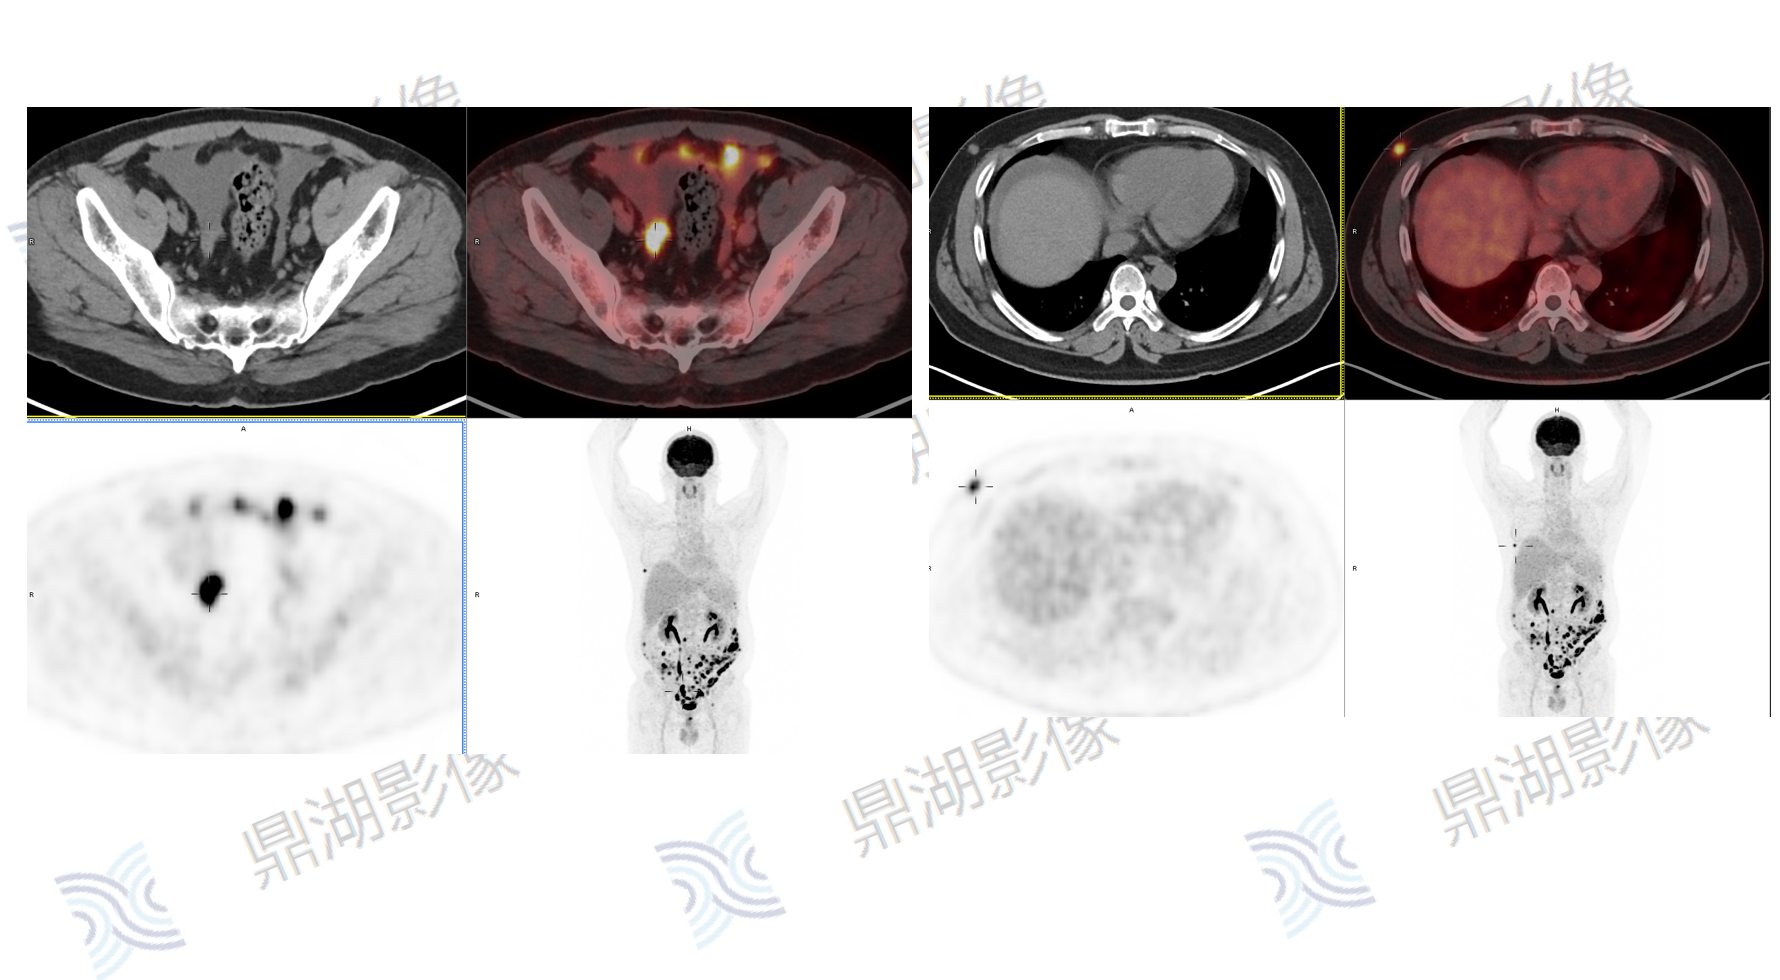

腹部上皮样间皮瘤

主诉:腹痛10天,CT检查示腹膜结节及肿块,腹腔积液;血红蛋白减低